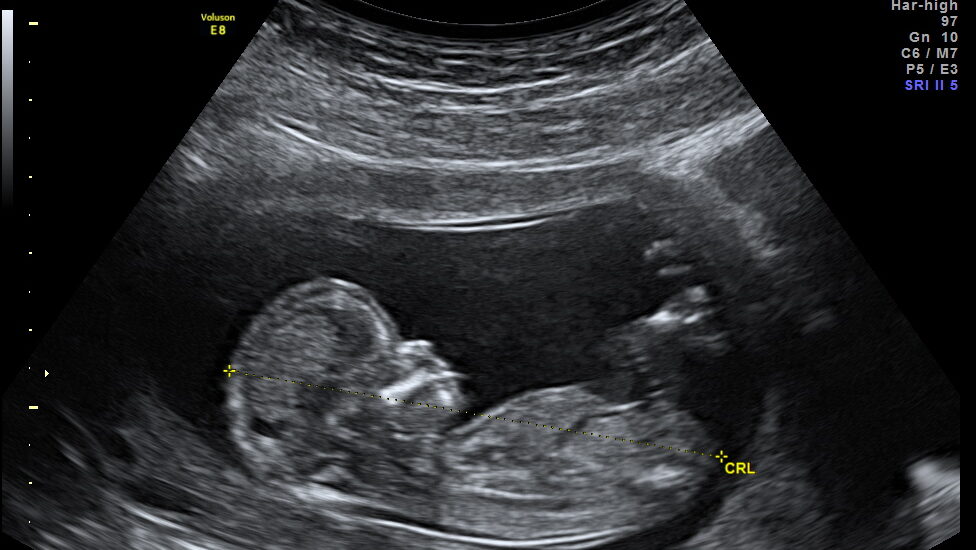

El trabajo analizó datos de nacimientos entre 2011 y 2017 y realizó un seguimiento hasta 2021, clasificando a las madres según su historial tiroideo y la evolución de sus niveles hormonales durante el embarazo. Los investigadores también detectaron que cuanto más prolongado fue el desequilibrio a lo largo de los trimestres, mayor fue el riesgo observado.